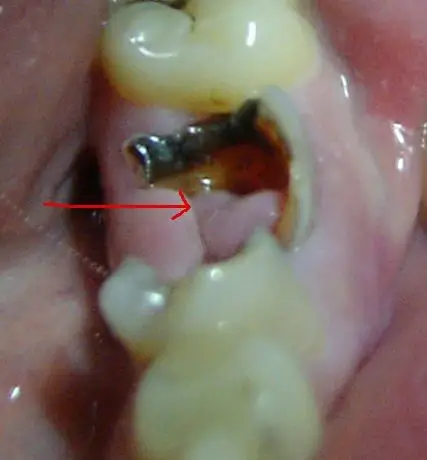

得了牙息肉(有图),能自愈吗?怎么治疗?要拨牙,要手术吗?